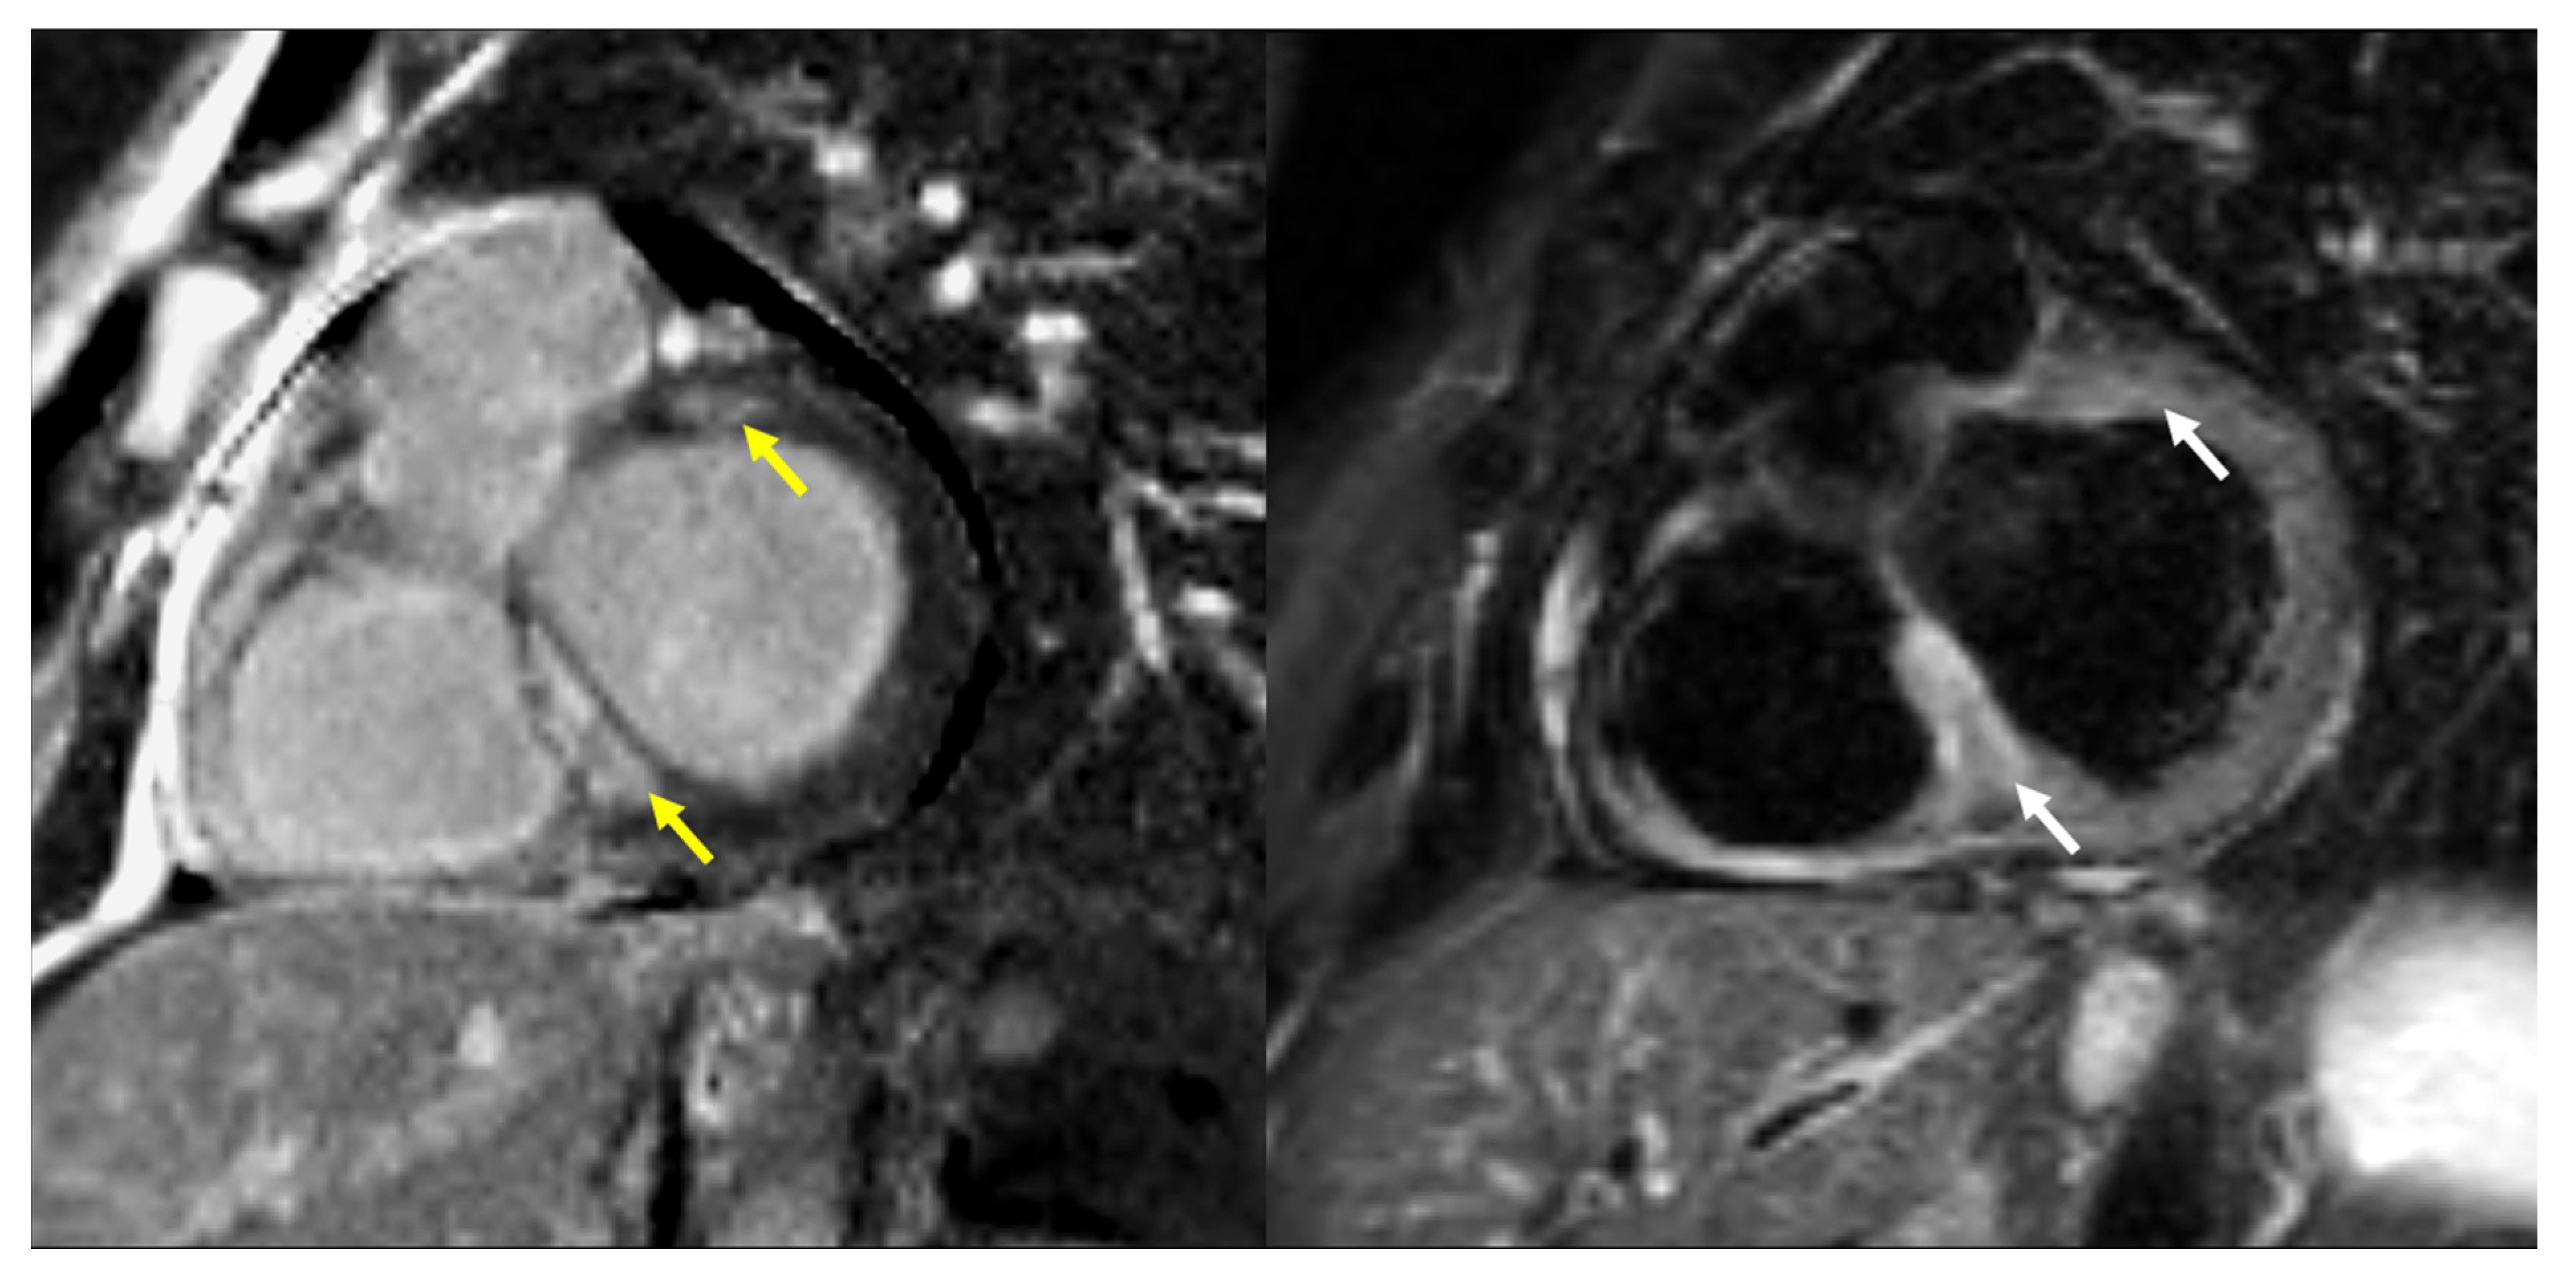

2. Materials and Methods

2.3. Screening and Diagnostic Procedures of CS